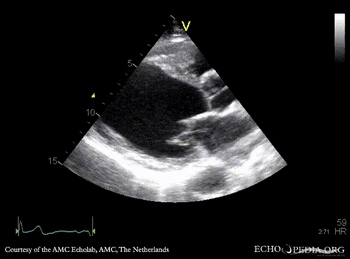

Apical aneurysm of LV

PLAX: dilated left ventricle, apical aneurysm PSAX: dilated left ventricle, reduced function